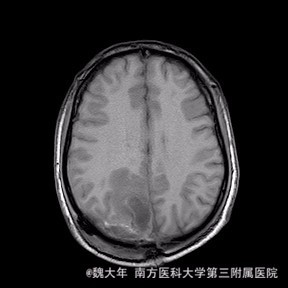

52岁,女性,因“反复头痛10余年,加重1年”入院。患者10余年前无明显诱因始出现头痛,表现为全头发作性胀痛,反复发作,无伴头晕、恶心,无呕吐、肢体抽搐,自行服药(具体不详)及休息后缓解,未予特殊处理。1年前患者觉头痛逐渐加重,以右顶部为甚,劳累或日晒后加重,无头晕、视物旋转,无恶心、呕吐,无发热、寒战,休息或平躺后症状稍有缓解,自行服药不能改善,至当地医院就诊,查颅脑MRI和CT提示“右侧顶部脑膜瘤”。

行“右顶开颅右顶部矢状窦旁脑膜瘤切除术”。取右顶马蹄形手术切口 ,颞侧翻开皮瓣,电刀切开骨膜,中线矢状缝上前、后极各钻一孔,颞侧后方钻一孔,铣刀铣一长方形(7*6cm)骨瓣,见硬膜表面较多点状渗血,予充分止血,悬吊硬膜。 显微镜下切除肿瘤:沿肿瘤边缘剪开硬膜后,见一大小约5*5*6cm肿瘤,沿硬膜内侧面呈匍匐状生长,边界与脑组织有蛛网膜分隔,质地较韧,基底与矢状窦关系密切,靠内侧与大脑镰粘连紧密,血供丰富。仔细分离肿瘤与脑组织的粘连,全切除肿瘤。肿瘤基底与矢窦粘连紧密,并破坏矢状窦侧壁,予低功率电刀反复烧灼,直至肿瘤无明显血供表现。严密止血后常规关颅。

术后1周复查头颅MR未见明显肿瘤残留,拆线后出院。